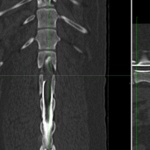

ダックスさんの後肢にふらつきがみられ、徐々に歩行障害が出てきているとのこと。かかりつけ医より椎間板ヘルニアが疑われるとのこと。ミエロCTで迅速検査を行うと脊髄圧迫病変が確認されたためL1~L2のHemi-Lamで脊髄除圧術を行いました。機能回復のためにリハビリテーションが計画されています。頑張ってくれました。